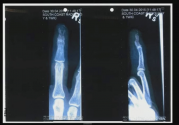

This X-ray is the bomb IMO.

You can talk & talk about an injury but to SHOW the person the damage is the key.

Also the nerve endings in the fingers & toes are not protected by much. Most people would CRINGE seeing this X-ray imagining the PAIN.

Expert witness Dr Richard Gilbert, a hand surgeon, tells the court he was asked to review the evidence relating to Johnny Depp's infamous severed finger injury, which happened in Australia in 2015.

The nature of Depp's injury was a fracture of the tip of the finger with "multiple pieces", which means there was some kind of "blunt force". The actor also sustained loss of tissue, the jury hears.

X-rays of Depp's hand are presented to the court and Dr Gilbert says he suffered a sharp laceration due to the "clean edges of the wound" and that it is an injury that was caused by "high velocity or force".

"I do believe so," the surgeon says, when asked if the injury could have been sustained in the way Depp has described.

He says Heard's story is "highly unlikely" as it would be "rare" for an injury such as Depp's to have been caused in this way. The actor would more likely have injured a different part of his hand, he says, and he saw no signs of this "whatsoever".

Asked why the injury is consistent with Depp's story, the surgeon says: "As Mr Depp described the bottle exploded so it's certainly reasonable that the glass that exploded as well led to the soft tissue loss."

Dr Gilbert says he agrees with "certain parts" of previous testimony by a previous doctor, Dr Richard Moore, but not all of it. Dr Moore said he disagreed with Depp's version of how the injury occurred, saying it was a "pinching" injury.

Dr Gilbert says there are two components to the injury - the fracture and the loss of soft tissue.

A pinch injury would lead to jagged borders in the remaining tissue, which isn't depicted in the pictures, the surgeon says. He adds that he believes a vodka bottle thrown from a distance would be "more than sufficient force" to result in the injury Depp sustained.

Dr Gilbert also says that thick glass from a bottle would not necessarily lead to glass shards being in the wound.

"Nobody can definitively state" how the injury occurred, he tells the court.